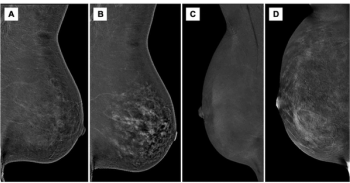

New research shows that premenopausal status, lactation, and hormone replacement therapy (HRT) all lead to higher background parenchymal enhancement grades on contrast-enhanced mammography.